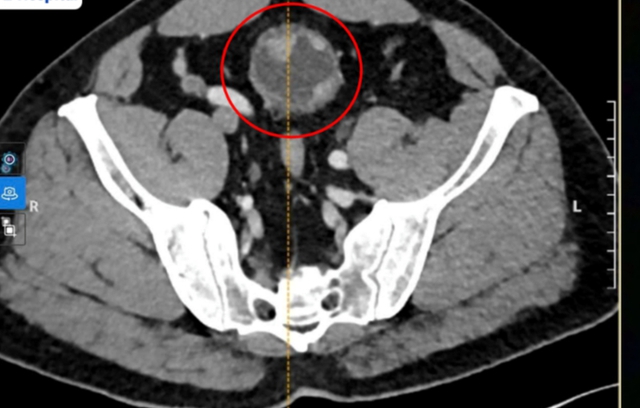

Khi đến khám tại Bệnh viện Đa khoa Tâm Anh TP.HCM, bác sĩ siêu âm và nội soi phát hiện khối u trong bàng quang kích thước khoảng 4–6 cm. Kết quả sinh thiết xác định đây là khối u ác tính, đã xâm lấn vào lớp cơ bàng quang.

Hình ảnh CT ghi nhận khối u to bất thường xâm lấn cơ bàng quang người bệnh. Ảnh: BVCC